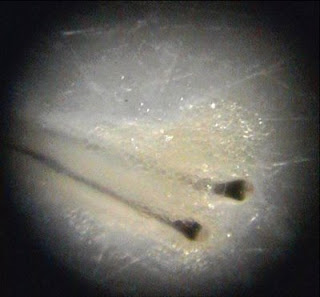

Separarea unitatilor foliculare se face cu mare grija folosindu-se microscop cu fibra optica pentru a evita caldura asupra foliculilor. Aceste unitati foliculare sunt pastrate intr-o solutie speciala la o anumita temperatura , pana cand doctorul specialist pregateste inciziile in zona numita „zona primitoare”. Se pot preleva pana la 4000 de unitati foliculare daca zona donatoare permite.

Piele cu par cum se observa sub microscop pregatita de separare a unitatilor foliculare.

Piele cu par cum se observa sub microscop pregatita de separare a unitatilor foliculare.Rezultate STRIP